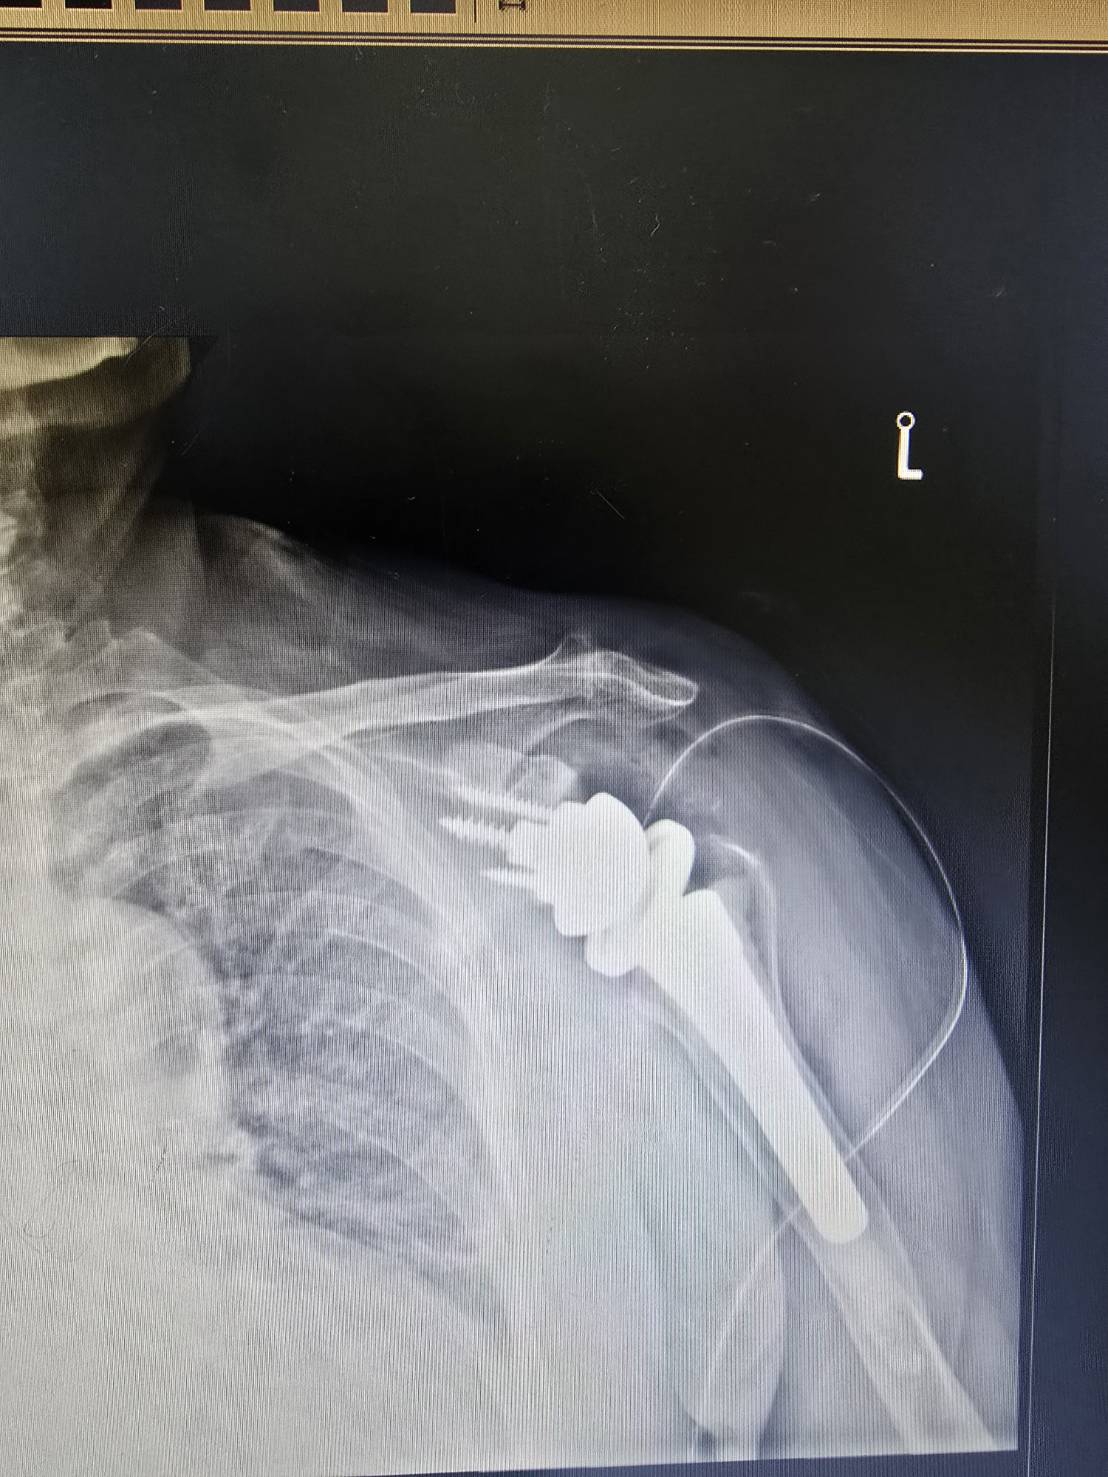

楊醫師最近也為一位這樣的病患,

完成了 Reverse Shoulder Arthroplasty——逆式人工肩關節置換手術。

事實上,當肩關節退化合併旋轉肌群嚴重損傷,傳統的肩關節置換往往無法解決問題——因為旋轉肌已經無力,裝了新關節也無法穩定運作。

這時候,逆式設計的巧妙之處就在這裡。

它把關節球與關節窩的位置對調,讓原本依賴旋轉肌的力學結構,改由三角肌來主導。

三角肌是肩膀最強壯的肌肉,即使旋轉肌嚴重耗損,三角肌依然能夠出力。

透過這個改變,肩膀重新獲得一個穩定的支點,疼痛減輕,活動範圍恢復,生活也跟著回來了。